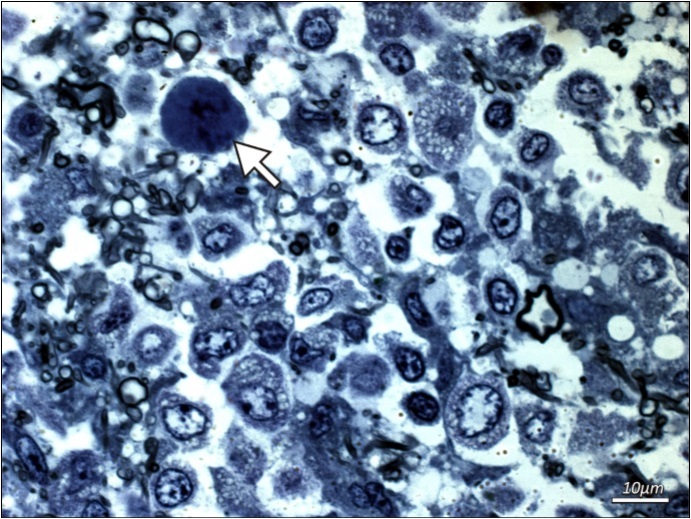

Additional examinations of post-mortem biopsy material taken from subcortical white matter (frontal and temporal lobe regions) by light microscopy LM and transmission electron microscopy TEM were performed. LM analysis of semi-thin sections confirmed the presence of demyelinating foci in the white matter region. Oligodendroglial cells that represent the main site of active JVC infection were found to have structural abnormalities. Particularly notable were enlarged nuclei of these cells and the presence of intranuclear inclusion bodies (Figure 2 and Figure 3). No lymphocytic infiltrations were found in the pathologically altered tissue. Electron microscopy only demonstrated slight post-mortem changes that developed during the 8-hour period between the patient’s death and the fixation of brain tissue. This enhances the value of the TEM results that showed inclusion bodies, i.e. aggregates containing nucleoproteins and virus-like bodies. The structures were located within interchromatin spaces in large oval-shaped oligodendroglial nuclei. The nuclear envelope had numerous isolated scattered enveloped viruses. High microscopic magnification (30-60,000 x) identified an electron-dense centre as viral DNA and an electron-lucent envelope as most likely protein capsid. The viral particles were round in shape, measuring 35-45 nm, and exhibited essentially no variation in shape or size. No fibre (rod) forms were observed. Virus-like particles were also present in the usually narrow strip of cytoplasm, however they were capsid-free.

Figure 2.Additional examinations of post-mortem biopsy material - light microscopy. Subcortical white matter from a patient with PML (routine blue-toluidine staining). Enlarged naked hyperchromatic nucleus of oligodendroglial cell infected with the polyomavirus (arrow) is demonstrated.